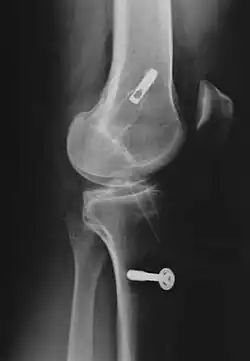

Le décollement ou l'arrachement du LCA de l'os est substantiellement plus rare que la rupture intraligamentaire[5] et n'est pas une rupture de ligament. Ce cas particulier survient plus fréquemment chez les enfants, particulièrement dans le domaine du tubercule intercondylaire du tibia, et possède en général, par refixation de l'arrachement par exemple avec des vis ou des fils métalliques, de bonnes chances de guérison complète.